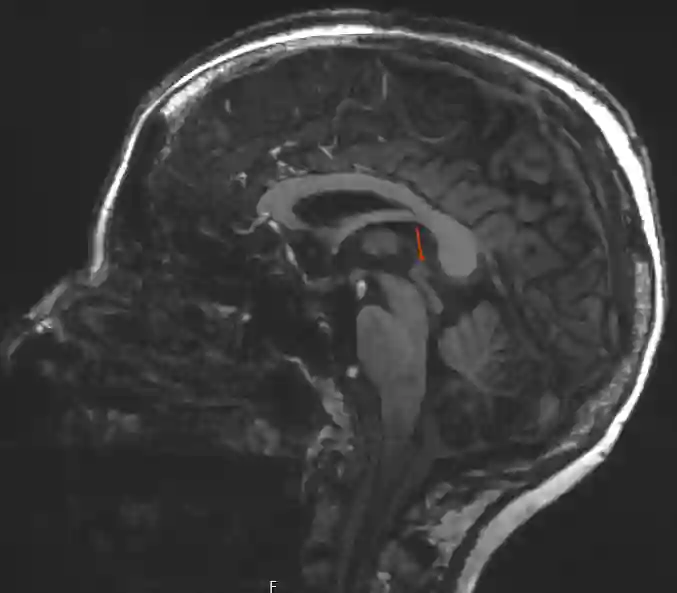

Glandula pinealis im MRI

Darstellung der Glandula pinealis in einer sagittalen T1 Sequenz eines 7Tesla MRI.